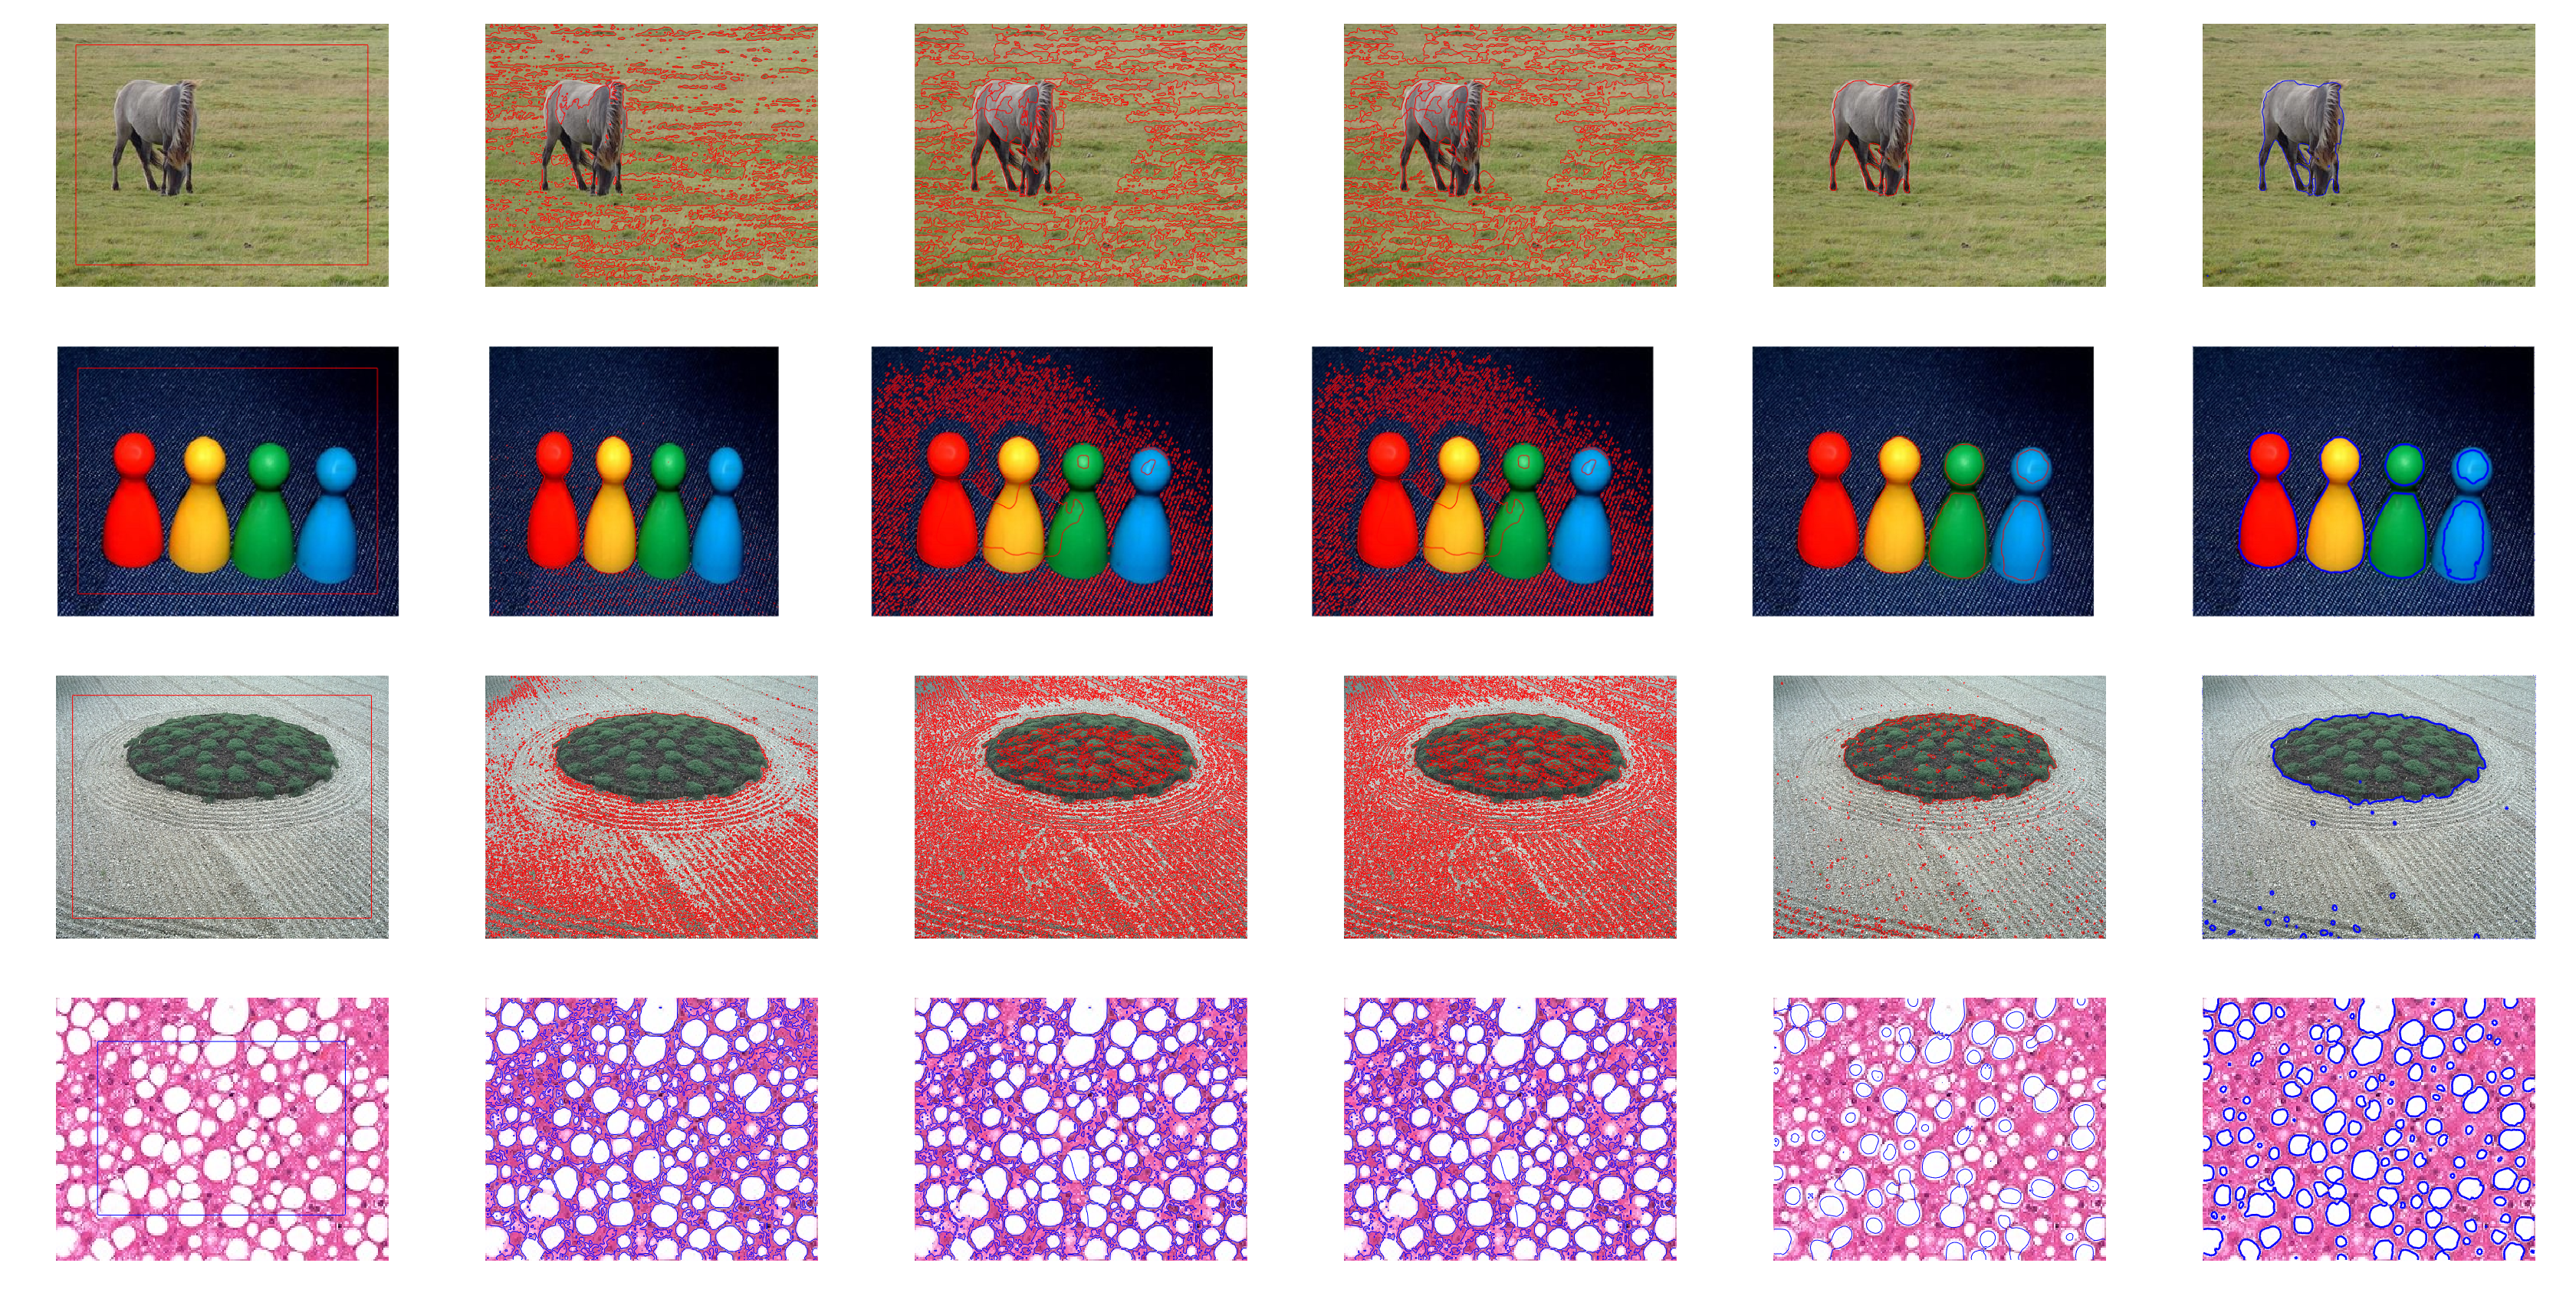

We further tested our model by segmenting color images. Figs. (12) and (13) show the segmentation of the color image datasets. In Fig. (12), the first three images are chosen from the MSRA 1000 dataset [44][47]. The first column shows the original image with the initial contour, whereas the remaining columns are the results of the CV, LBF ,LIF, SDREL, and proposed models. The experimental results show that the CV, LBF, and LIF models are unable to segment the object from the color images, whereas SDREL shows prominent results. However, the segmentation results of our model on the MSRA dataset are more accurate and reliable. Similarly, the last row of Fig.(12) shows a fatty liver image in which the purpose of the segmentation is to extract the fatty circle from the image. All the applied models extract some parts of the fats from the liver, whereas our model achieves the best segmentation and extracts all fat circles from the liver image. However we still have gap to improve the segmentation accuracy of the region based ACMs such color images.